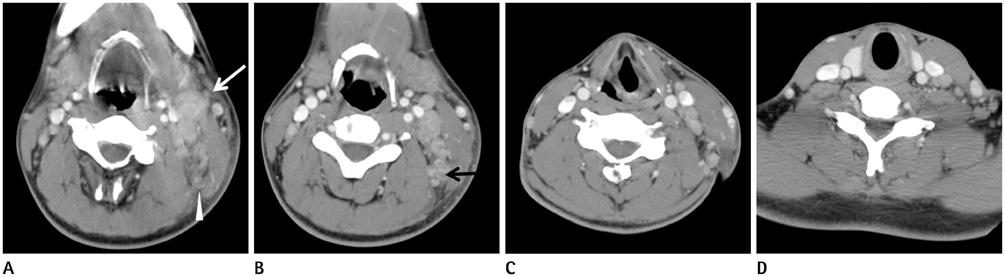

To compare the clinical and CT manifestations of Kikuchi disease (KD) and tuberculous lymphadenitis (TL).

KD patients showed a female predominance (67.1%). Patients with TL were older. Leukocytopenia and increased ESR were more frequent in patients with KD. KD more commonly affected lymph nodes in level II, III, and V, while TL more commonly involved lymph nodes in the upper paratracheal area. Perinodal fat infiltration was more frequent in KD. Muscle abscess was seen in patients with TL only (14%). Necrotic lymph nodes were more frequent in TL. A thin type was more frequent in TL.

KD showed female predominance, leukocytopenia, increased ESR, involvement of levels II, III, and V and frequent perinodal fat infiltration. TL patients were older than KD patients, were commonly affected in the upper paratracheal area, abscesses were shown only in this group and thin type necrotic lymph nodes were more frequent.